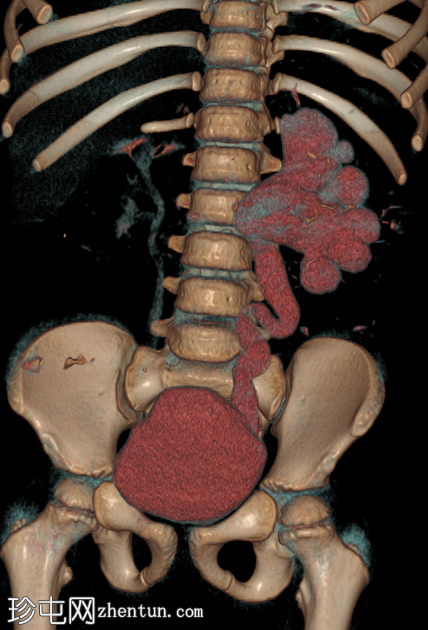

轴位

平扫

在这张多期增强CT图像中,我们可以观察到肾盏、肾盂以及左侧输尿管全程扩张。

未见感染或其他相关征象。

本例为原发性巨输尿管。整个泌尿系统的扩张是诊断的关键。